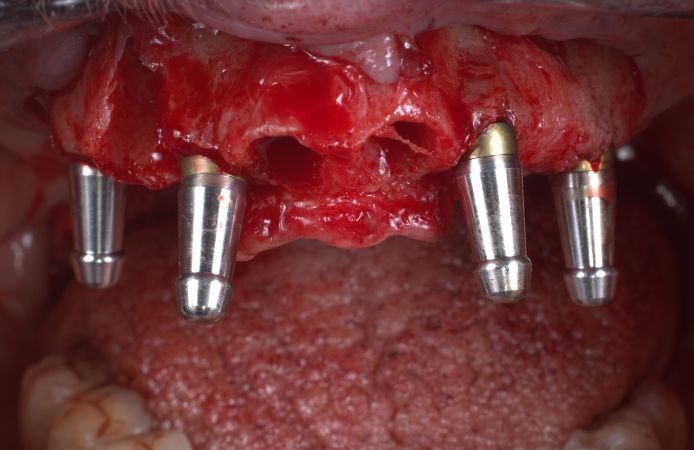

Figure 5.

Four Neoss ProActive Edge implants were immediately installed. The anterior implants were 4.0 x 15 mm.

Figure 6.

The two posterior implants (4.5 x 15 mm) were tilted to maximize the distance between the implants, to avoid the sinus, to maximize the contact with available bone, and to increase stability.

Figure 7.

Occlusal view of the placed implants